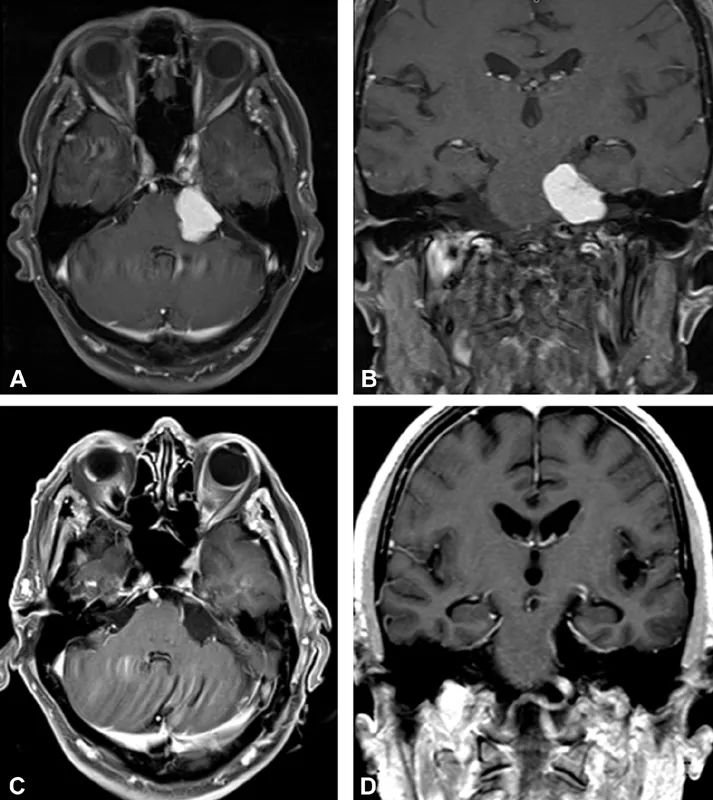

这位81岁的老先生就医时,说自己左边脸发麻、走路不稳已经有3个月了。详细检查,发现左边脸颊确实感觉有些迟钝,走路时摇摇晃晃不太稳当。拍头部核磁共振,结果发现左侧桥小脑角(CPA)区长了个巨大的肿瘤,把脑干都挤歪了(图1A、1B)。

手术很成功,老先生恢复得特别好,术后未出现新的神经功能障碍。术后病理示WHO Ⅰ级脑膜瘤。复查MRI证实肿瘤已全切除(图1C、1D)。老先生住院4天就出院回家了。术后1个月随访时,脸上不麻了,走路也稳当了,跟生病前没什么两样。

(A)术前桥小脑角脑膜瘤的轴位及(B)冠状位磁共振影像,可见肿瘤已对脑干造成显著压迫。(C,D)术后磁共振影像(C为轴位,D为冠状位)显示肿瘤已获大体全切除。